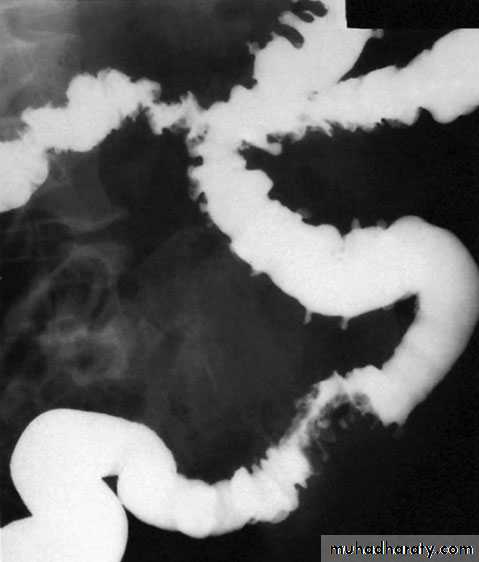

Jejunal diverticulaThese are usually of variable size and multiple (Fig. 65.8).Clinically, they may (1) be symptomless, (2) give rise to abdominalpain, (3) produce a malabsorption syndrome or (4) presentas an acute abdomen with acute inflammation and occasionallyperforation. In patients with major malabsorption problemsgiving rise to anaemia, steatorrhoea, hypoproteinaemia orvitamin B12 deficiency, resection of the affected segment withend-to-end anastomosis can be effective.

DiverticulosisIt is important to distinguish between diverticulosis, which maybe asymptomatic, and clinical diverticular disease in which thediverticula are causing symptoms. On histological investigation,the diverticulum consists of a protrusion of mucous membranescovered with peritoneum. There is thickening of the circularmuscle fibres of the intestine, which develops saw-tooth appearance on barium enema

Barium enemas and sigmoidoscopy are usuallyreserved for patients who have recovered from an attack of acute diverticulitis, for fear of causing perforation or peritonitis. Watersoluble contrast enemas may, however, be helpful in sorting out patients with large bowel obstruction. In the acute situation, it is good at detecting intraluminal changes and leakage. The sensitivity for this is of the order of 90%. Barium radiology is carried out to exclude a carcinoma and to assess the extent of the disease.

Where the sigmoid colon is thickened and narrowed, a ‘sawtooth’ appearance may be seen. Some strictures can be very difficult to distinguish by radiology alone and, in those circumstances, colonoscopy will be necessary to rule out a carcinoma. Vesicocolic fistulae should be evaluated with cystoscopy and biopsy in addition to colonoscopy. Contrast examinations may show the fistula itself. The differential diagnosis for vesicocolic fistulae (and other fistulae) includes cancer, radiation damage, Crohn’s disease (CD), tuberculosis and actinomycosis.